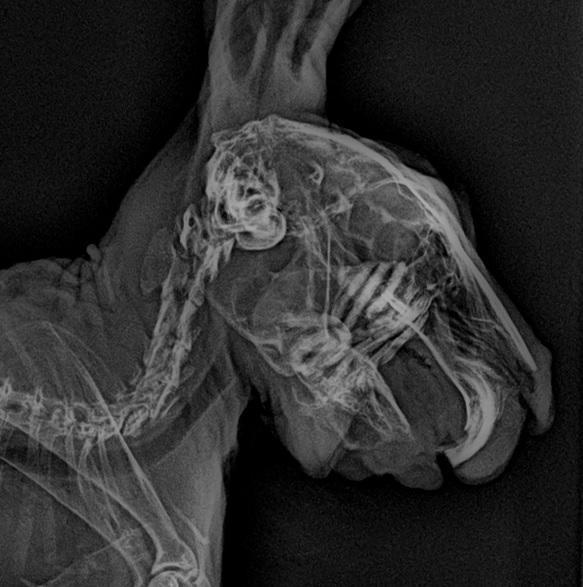

門牙感染、充滿膿液

牙根過長(食物太過多樣化、兔兔挑食誘發只食甜食,拒食硬草)

2. 影像檢查:X 光可評估腸道氣體、糞塊位置和牙齒結構;或需鎮靜。

• 牙科問題:在麻醉下修整牙齒,移除尖刺,或處理牙根膿腫。術後需服用止痛及抗生素。